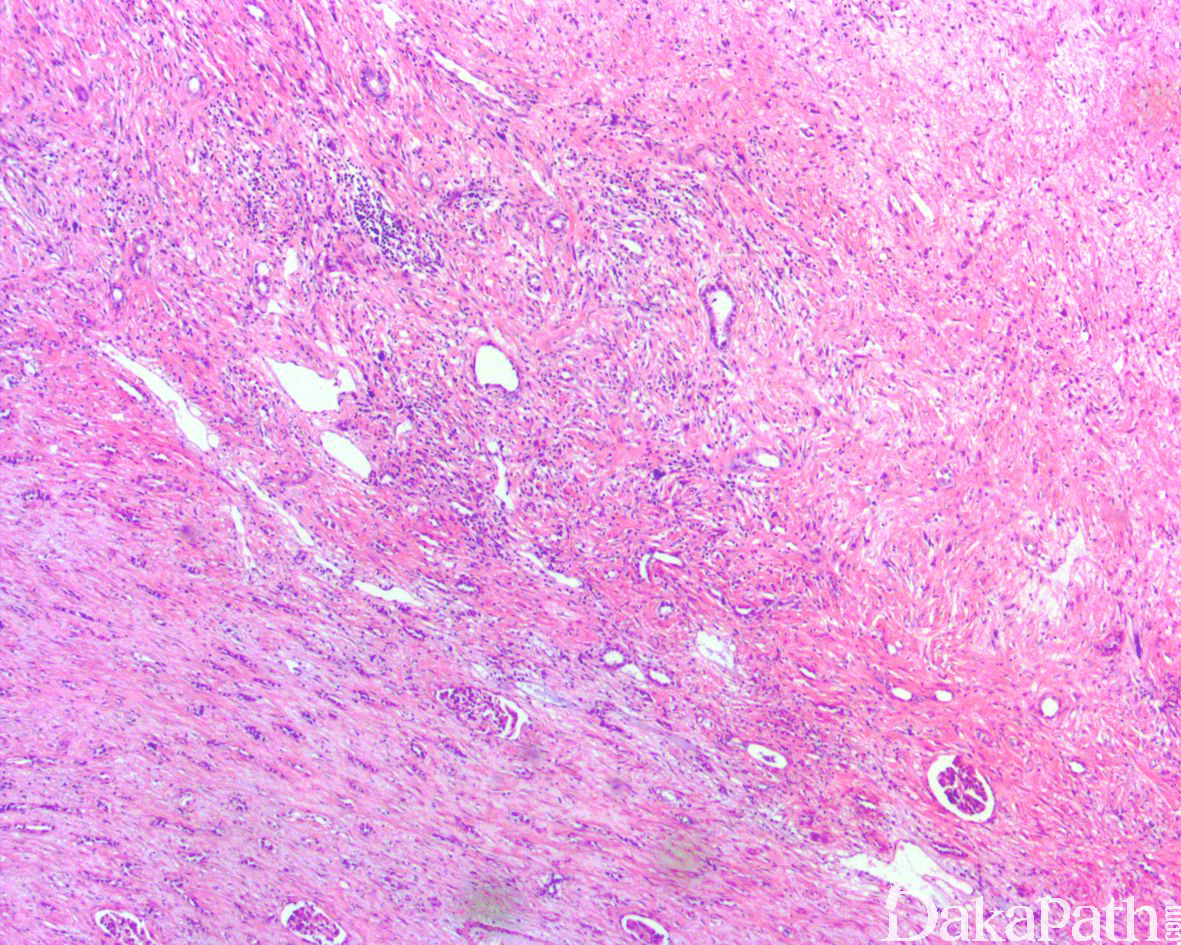

如前所述,DDLPS 组织学上通常表现为 ALT/WDLPS 成分向非脂肪源性的肿瘤成分转化,2 种成分在镜下通常分界较清楚,表现为突然的过渡;但有时可表现为逐渐的过渡或在整个肿瘤内交错的分布(马赛克样的去分化),这一情况尤其在伴有低级别去分化时常见。肿瘤可能部分带假包膜或边界清楚,但至少局部可见推挤状或浸润性边界,后腹膜的 DDLPS 常见累及周围实质器官(如肾脏等)。高分化与去分化成分的比例在不同肿瘤内多少不等,有时候即使在广泛取材的情况下高分化成分也可能完全确如,而去分化成分通常较广泛,但有时也可能仅仅不足 1 cm(又称为微小去分化)。DDLPS 中的 ALT/WDLPS 组织学类型以脂肪瘤样和硬化性为主,而去分化成分大多数表现为高级别去分化特征包括高级别多形性肉瘤样(多形性瘤细胞伴有席纹状排列类似于多形性未分化肉瘤/恶性纤维组织细胞瘤)、高级别梭形细胞肉瘤样(细胞密度较高的梭形瘤细胞伴有交错束状或鱼骨样排列类似于纤维肉瘤)以及少见的高级别圆细胞肉瘤样(弥漫的小蓝圆细胞类似于骨外尤文肉瘤或差分化的滑膜肉瘤)和上皮样特征(弥漫成片的上皮样瘤细胞伴有丰富的嗜酸性胞质或横纹肌样特征类似于转移性癌或恶性间皮瘤),高级别去分化成分通常瘤细胞密度高,间质稀少,核分裂象活跃(> 5 个/10 HPF),但比较于与之类似的肿瘤而言,去分化成分的核分裂象相对较少;坏死较为常见。

少数情况下,去分化成分可表现为低级别去分化组织学特征包括低度恶性纤维黏液肉瘤样、纤维瘤病样、炎性肌纤维母细胞瘤样以及孤立性纤维性肿瘤样等,低级别去分化成分瘤细胞以纤维母细胞样细胞为主,密度相对较低,间质较丰富,核异型性轻-中度,核分裂象< 5 个/10 HPF,罕见坏死。在后腹膜和腹部盆腔等部位的 DDLPS 可表现明显的间质黏液变性,特别是低级别 DDLPS,局部的黏液变性可导致稀疏的瘤细胞于血管周聚集从而类似于低级别黏液纤维肉瘤,而广泛的黏液变性导致局部的丛状小血管聚集和肺水肿样组织间隙使得 DDLPS 可能非常类似于黏液样脂肪肉瘤。另一少见而特殊的 DDLPS 特征为脑膜上皮样漩涡伴有化生性的骨形成,组织学上表现为低级别的梭形或胖梭形瘤细胞围绕中央小血管呈同心圆状或洋葱皮样排列,类似于脑膜瘤中常见的漩涡样结构,在漩涡的周围常见伴随的化生性骨形成。该组织学特征常出现在低级别去分化的 DDLPS 中,尽管罕见,但当其出现的时候具有高度的诊断提示作用。